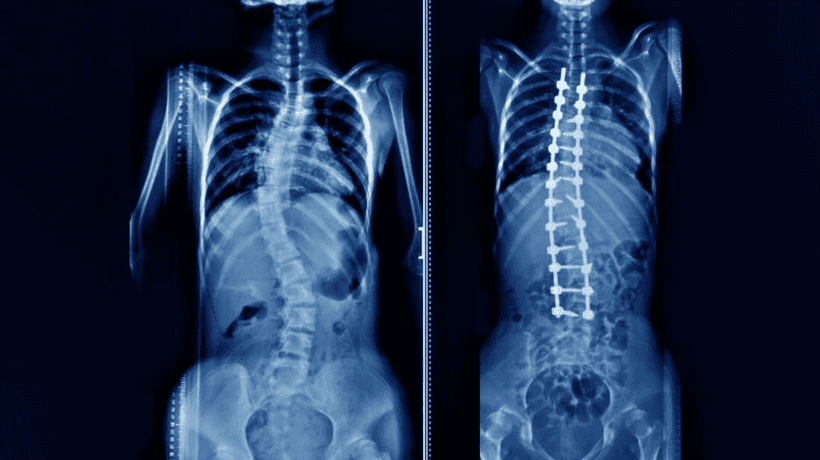

Tim Perjalanan KesehatanSkoliosis adalah kelengkungan yang berhubungan dengan tulang belakang yang terjadi selama masa pertumbuhan dan sesaat sebelum pubertas. Skoliosis dapat mengambil kurva yang buruk karena kelumpuhan serebral, dan distrofi otot, yang penyebabnya tidak diketahui. Sebagian besar kasusnya ringan, dengan beberapa gejala yang diketahui. Komplikasi menjadi menonjol saat anak -anak tumbuh. Terkadang ada persyaratan untuk operasi, di lain waktu penjepit berfungsi seperti keajaiban untuk penyebabnya.

Itu pengobatan Skoliosis bukanlah hal yang mudah karena berkaitan dengan tulang belakang yang merupakan rangkaian tulang paling kritis dalam tubuh. Kondisi pasien rawan skoliosis berkisar antara baik hingga sedang. Itu tergantung pada seberapa awal masalah telah didiagnosis dan dirawat dengan aman.

Bedah Skoliosis

- Operasi harus menghentikan kelengkungan tulang belakang

- Skoliosis dapat mempengaruhi Jantung dan Paru-paru. Kerusakan terjadi bila kelengkungan tulang belakang 70 derajat. Kurva 100 derajat dapat menyebabkan kerusakan parah pada posisi jantung dan paru -paru.